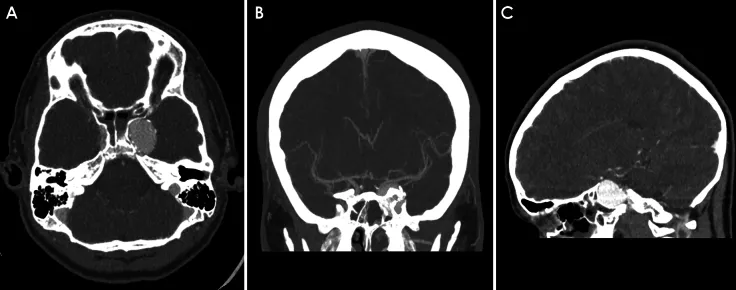

CT血管造影轴位、冠状位及矢状位图像清晰显示左侧颈内动脉海绵窦段巨大型动脉瘤伴随蝶骨重塑改变,蛛网膜下腔未见出血征象。

随访数字减影血管造影影像显示:侧位投影基底动脉顶端动脉瘤未见显影;3个月随访CT血管造影轴位图像证实基底动脉顶端动脉瘤完全血栓形成,左侧颈内动脉海绵窦段动脉瘤保持稳定。